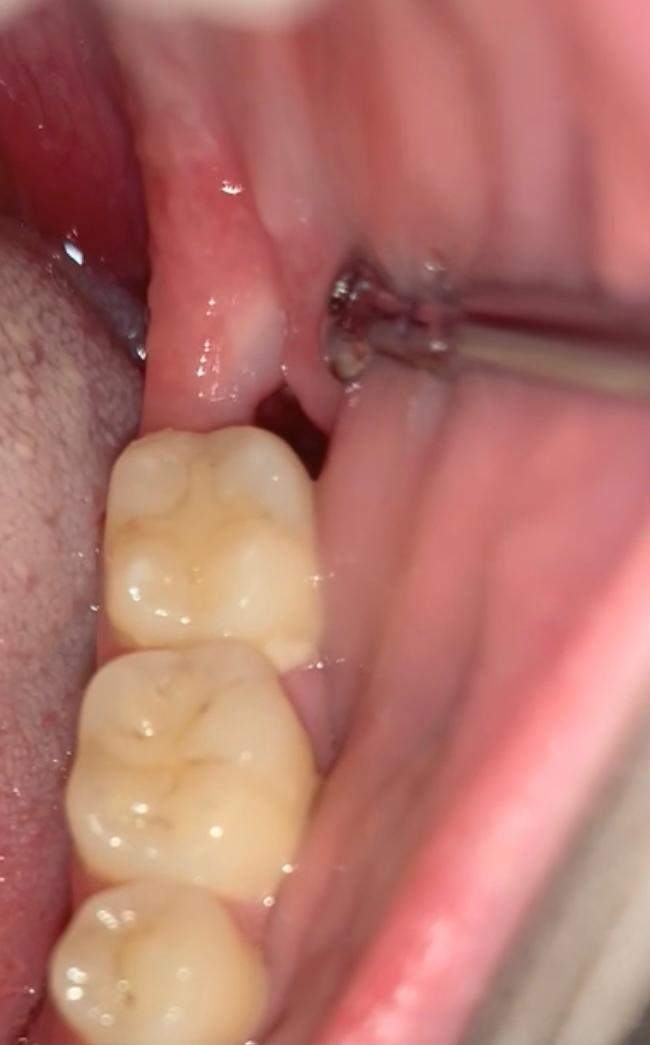

Nikotin kann zur Entzündung der Wunde führen, die dann nicht ordnungsgemäß verheilen kann. Meine Weisheitszähne waren schon länger am Durchbrechen und das Zahnfleisch öfters entzündet. Sind die Weisheitszähne entzündet oder durchgebrochen, müssen sie in der Regel vollständig gezogen werden. Deshalb ist bei vielen Menschen der Platz im Mundraum für die Weisheitszähne unzureichend.Schmerzen und Schwellungen sind nach der Entfernung der Weisheitszähne normal. Keine harten Speisen wie Vollkornbrot essen, weil . Dafür, dass ich echt Panik davor hatte, war es eigentlich total easy. Kategorie Erfahrungsberichte, Neutral.Die Entfernung der Weisheitszähne ist eine häufige zahnärztliche Intervention, die oft notwendig ist, um verschiedene Probleme zu verhindern oder zu lindern. Unser Körper sorgt mit dem Wundschorf selbst dafür, dass die Wunde vor äußeren Einflüssen geschützt ist und heilen kann. Blutverdünnende Medikamente wie Aspirin dürfen nach dem Eingriff nicht genommen werden.Viel Patienten fragen, wie Sie sich nach einer Weisheitszahn-OP verhalten sollen. Von den Kühlpads bis zur passenden Zahnbürste zum Zähneputzen lassen sich schon sehr viele Dinge vorbereiten, um den Heilungsprozess zu beschleunigen und Beschwerden nach der Weisheitszahn OP zu . Viel Trinken ist auch nach der Weisheitszahnentfernung wichtig! In den ersten Tagen allerdings auf Alkohol, koffeinhaltige Getränke (können zu Nachblutungen führen) und Säfte mit hohem Fruchtsäureanteil (z.2023) Simon, 32: Man muss schon Murphys Law abbekommen ansonsten geht es (04. Zudem können Sie einige Vorkehrungen treffen, um die Wundheilung zu fördern und Infektionen zu vermeiden. Im Rahmen der Evolution wurden die Kiefer der Menschen immer schmaler und graziler, während sich die Zahngröße nur unwesentlich veränderte.

Während der Ablauf der Weisheitszahn OP am Oberkiefer meist reibungslos vollzieht, kommt es bei der Extraktion am Unterkiefer häufiger zu leichteren Problemen.